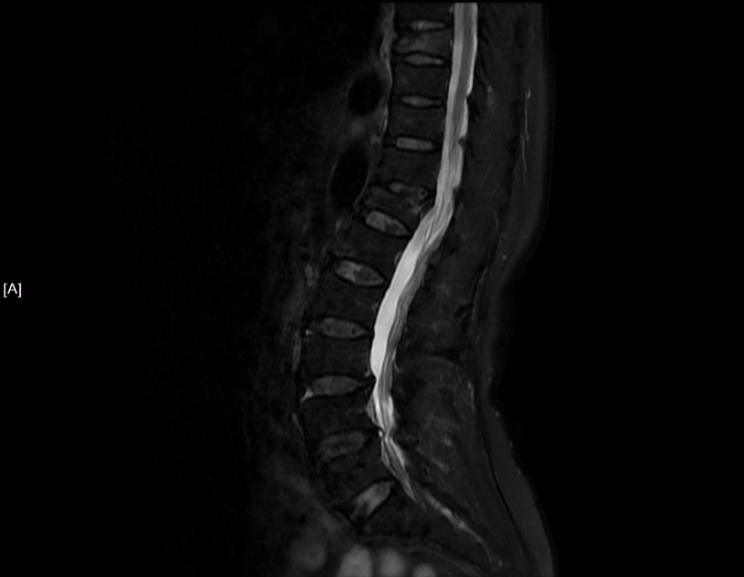

吴老太太今年86岁,同时患有心脏病、老慢支、哮喘、糖尿病等多种疾病,不久前因为并发心衰、呼衰在独墅湖医院经抢救后脱离危险。然而不巧的是,几天前自己在家只轻轻扭了一下腰,就感觉背部疼痛难忍,寝食难安。于是来到我院骨科就诊,医生怀疑是脊柱骨质疏松性骨折,安排收治住院,对病患进行磁共振检查后证实是“第8胸椎压缩性骨折”。

医生在诊断后决定行经皮椎体后突成形术(简称PKP术),需要病人在全身麻醉下俯卧位,医生在全程透视下完成手术。对于一般的患者来说不成问题,而对吴老太太而言却难以实施。首先,她的全身情况较差,心肺功能不全,基础疾病多且严重。入院时就有明显的呼吸困难,氧饱和度只有70%左右,很难耐受全身麻醉。即使勉强度过手术阶段,术后也可能要气管插管,靠呼吸机维持生命,肺部感染则难以控制。其次,如果采用局部麻醉俯卧位手术,尽管可以规避全麻的风险,但该患者根本不能承受俯卧位对心肺功能的影响。但如果不采取手术,卧床以及日夜不停的疼痛对已经遭受过心衰和呼衰的吴老太太来说是雪上加霜。

在常规办法难以实施时,独墅湖医院骨科的医生们决定另辟蹊径,挽救病患生命。常规手术主要面临两大难题:全身麻醉与俯卧位。那么如果采用局部麻醉与侧卧位呢?对!这就是解决问题的关键!局麻可以规避全麻的风险;侧卧可以避免俯卧对心肺的影响。如此,问题似乎迎刃而解了。但是,这样的改变,尤其是侧卧位完成PKP术,导致空间位置变了,手术的难度大大增加了。而且,吴老太太耳背,局麻侧卧位手术需要病人的配合,术中的沟通也是一个问题。尽管困难重重,这也是挽救老人家生命的唯一可行的办法。